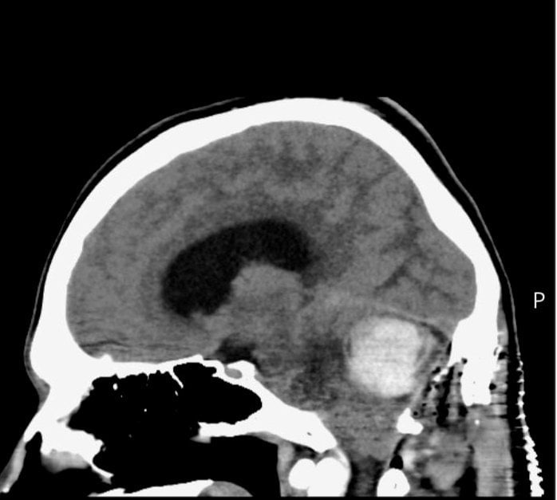

Luke Taylor's brain scan. (Nia Jones via SWNS)

kAmw6 56>2?565 2? |#x D42? 2?5 E96 C6DF=ED 42>6 324< D9@H:?8 E92E {F<6 925 2 926>2?8:@3=2DE@>2  \ 2 G6CJ C2C6 k2 9C67lQ9EEADi^^E2=<6C]?6HD^a_ae^_b^`_^>2?D\=@4<5@H?\2?I:6EJ\EFC?D\@FE\E@\36\3C2:?\EF>@C^Q E2C86ElQ03=2?<Q C6=lQ?@C676CC6C ?@@A6?6CQm3C2:? EF>@Ck^2m E92E 42? 8C@H E9C@F89@FE E96 3C2:? 2?5 DA:?2= 4@C5]k^Am

kAmqJ E96 E:>6 @7 5:28?@D:D[ E96 EF>@FC 925 8C@H? D@ =2C86 \ 3:886C E92? 2 8@=7 32== \ E92E {F<6 H2D E@=5 96 @?=J 925 52JD E@ =:G6 H:E9@FE 6>6C86?4J DFC86CJ]k^Am